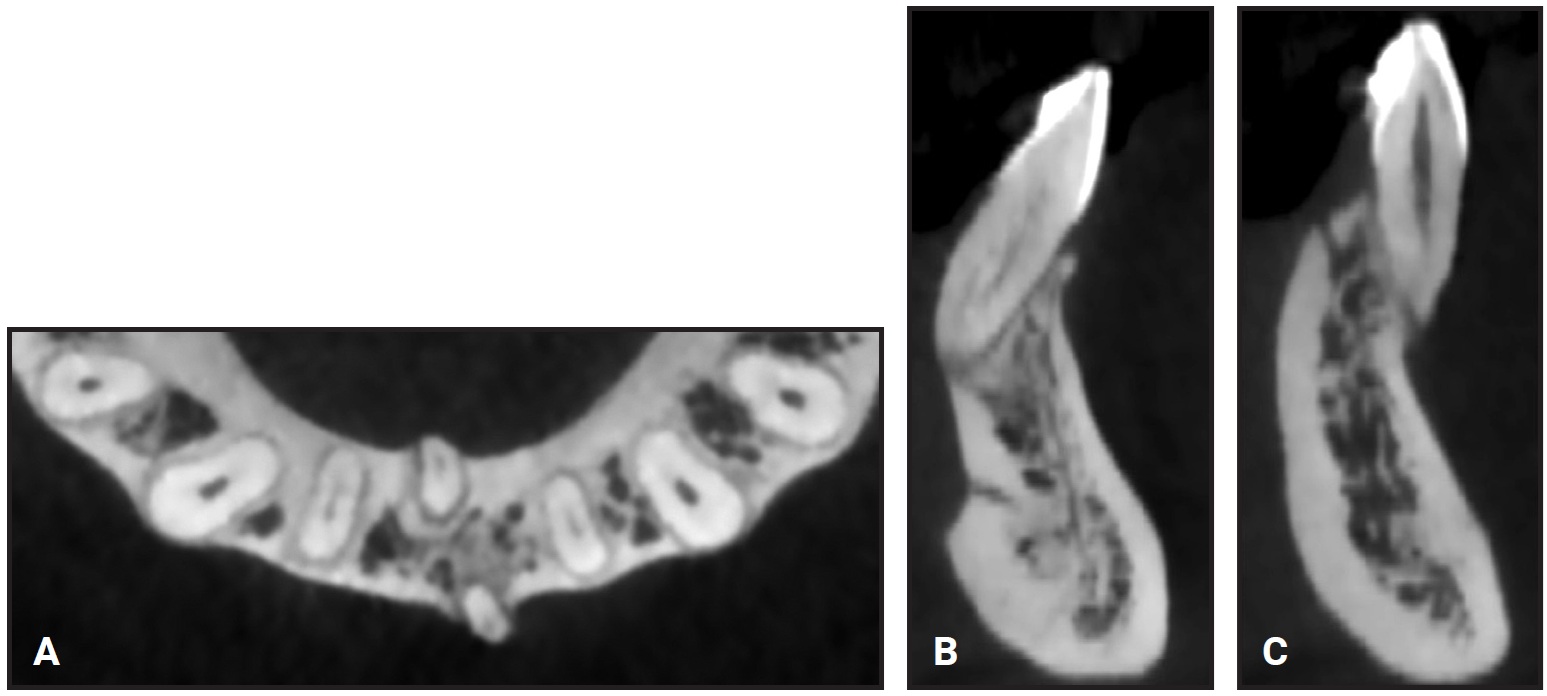

A 32-year-old female was evaluated by a periodontist and referred to the Department of Orthodontics at the University of Bologna (Fig. 2). She requested correction of her poor esthetics and relief from the marked dental sensitivity caused by gingival recession on the lower left central incisor, which seemed buccally displaced. The patient’s general dentist had tried to cover the recession, but advised that the tooth needed to be extracted. CBCT showed the root of the lower left central incisor outside its buccal cortical bone and the root of the lower right central incisor outside its lingual cortical bone (Fig. 3).

Fig. 3 A. Displaced lower central incisors. B. Right incisor outside lingual cortical bone. C. Left incisor outside buccal cortical bone.